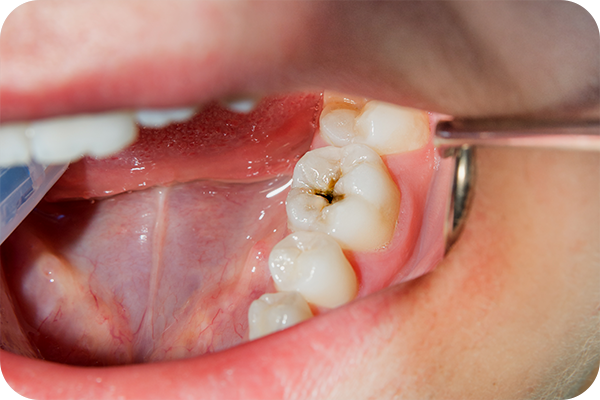

一般歯科では、むし歯や歯周病など、多くのかたが経験される身近なお口のトラブルに対応しています。これらの症状は放置すると進行し、むし歯は元の状態に戻ることはなく、歯を失う原因になることもあります。歯の痛みや違和感など、少しでも気になる症状がある場合は、我慢せずに早めに歯科医院を受診し、適切な診断と治療を受けることが大切です。

カリエスチェッカー

むし歯の部分だけを染め出すことができる検知液です。健康な歯との境目をはっきり確認できるので、削りすぎやむし歯の取り残しを防ぐのに役立ちます。